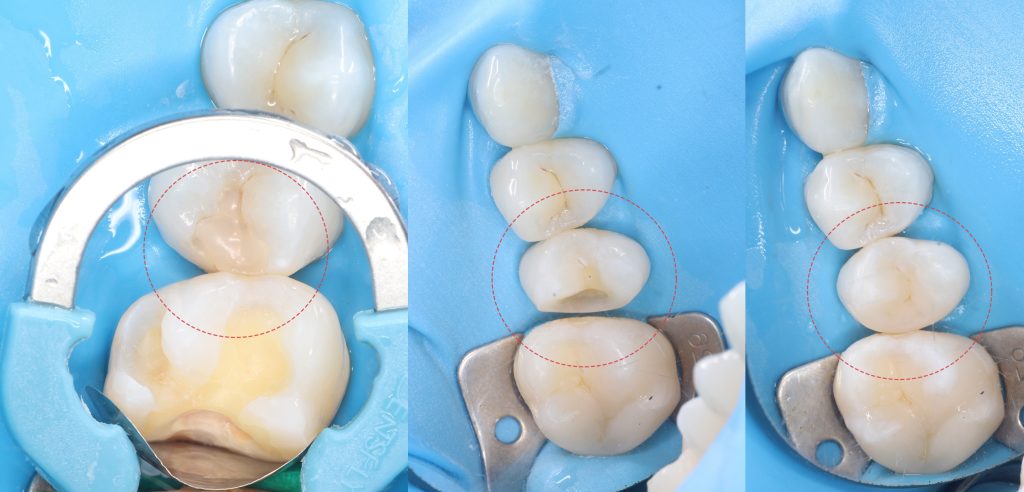

During a clinical examination, it is difficult to verify the presence of caries located under a filling, which is why the information obtained during a radiological examination is so important

Please note that despite the fact that the radiolucent area is poorly visible when viewing CBCT, Diagnocat reflected in the report the presence of signs of caries and accurately indicated the localization